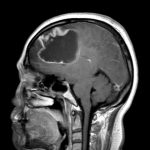

断層撮影

No.’25_45 手術前1

No.’25_45 手術前2